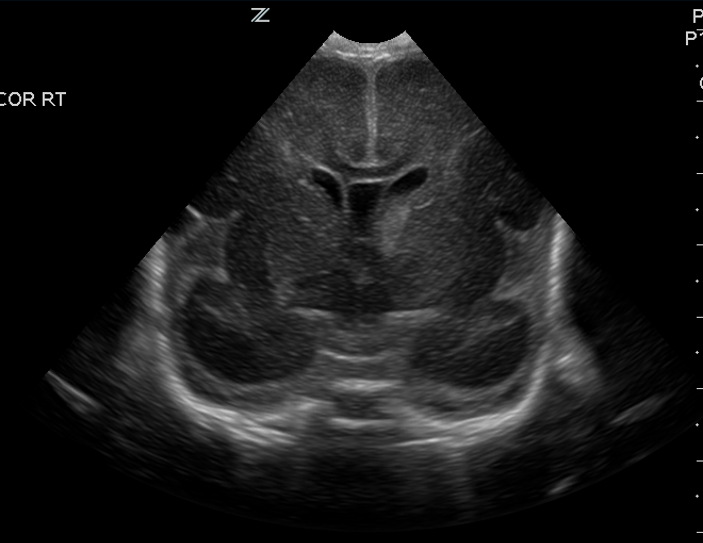

Brain

The brain is immature. [Yes/No]

There is under-sulcation and open sylvian fissures. [Yes/No]

CSF spaces/ventricular system

There is prominence of the ventricular system. [Yes/No]

There is a cavum septum pellucidum. [Yes/No]

The lateral ventricle/s are dilated. [Yes/No]

The third ventricle is dilated. [Yes/No]